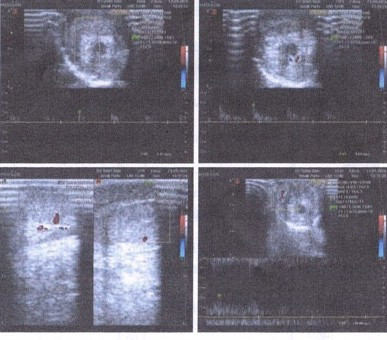

"Phải nối từng mạch máu rất nhỏ nên ca phẫu thuật phải tiến hành dưới kính vi phẫu, chỉ khâu cũng phải chuyên biệt", bác sĩ Dũng chia sẻ. Đây là trường hợp nối dương vật nhỏ tuổi nhất bệnh viện thực hiện. Sau 2 tuần phẫu thuật, bé trai hồi phục khỏe mạnh. Kết quả kiểm tra cho thấy chức năng tiêu tiểu, tưới máu của dương vật đều rất tốt.

Hình ảnh kiểm tra sau mổ cho kết quả hồi phục tốt. Ảnh bệnh viện cung cấp.